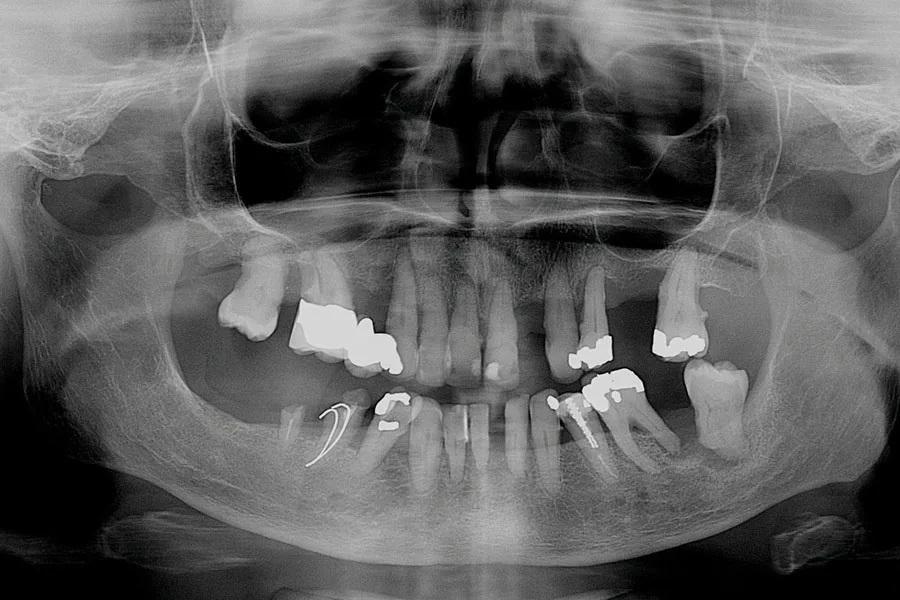

В апреле 2017 года 74-летняя пациентка обратилась с жалобой на то, что «все шатается» (Фото 1 и Фото 2). В анамнезе — гипертония и лечение рака груди в 2002 году с удалением левой молочной железы, но противопоказаний к стоматологическому лечению не было. Пациентка принимала Avapro и Pravachol и имела аллергию на пенициллин.

Фото 2: Рентгенограмма до лечения.

Пациентка испытывала сильный страх перед стоматологическим лечением, что усугубило состояние ее зубов. У нее были частичные съемные протезы на верхней и нижней челюстях, а оставшиеся зубы имели запущенный пародонтит, кариес и подвижность. На панорамном снимке все зубы были признаны не подлежащими восстановлению (Фото 2). Учитывая финансовые ограничения и страх перед хирургическим лечением с установкой имплантатов, было принято решение о цифровом изготовлении немедленных протезов. После заживления тканей временные протезы должны были быть заменены на окончательные. Из-за страха пациентка вернулась к лечению только через 3 года.